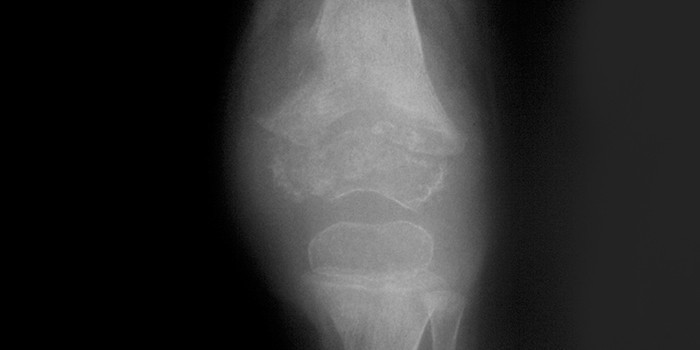

Одним из вариантов костно-суставного туберкулеза является туберкулезный артрит. Для этой патологии типично развития моноартрита крупного сустава или спондилита. Клинические признаки:

- субфебрильная лихорадка;

- интоксикационный синдром;

- формирование свищей с выделением казеоза;

- мышечные контрактуры;

- болезненные движения в суставе;

- деформация сустава;

- отек;

- мышечный гипотонус.